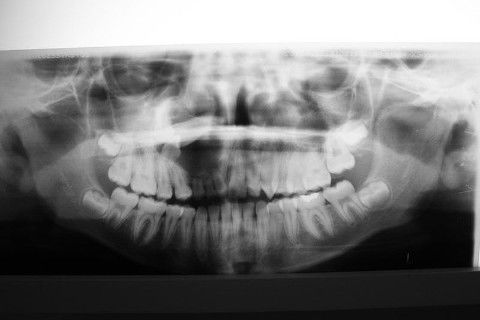

Rx panorâmica

Exames radiográficos sugerem imagem unicística, delimitada, circunscrita, 3 cm de extensão, associada aos dentes referidos acima.

As hipóteses diagnósticas incluem, a meu ver, cisto dentígero, cisto primordial, ameloblastoma;